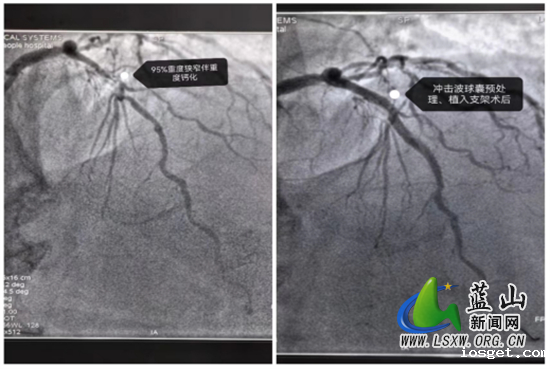

这位患者因为长达8年的反复胸痛,近5天内症状加重,严重影响了日常生活,因此前来华体会登陆网站中心医院就诊。经过详细的冠脉造影检查,确诊为冠心病,主要表现为三支血管病变,其中前降支95%重度狭窄并伴有弥漫性严重钙化,右冠动脉更是完全闭塞。钙化病变使得血管壁变得坚硬,传统的介入手段难以有效处理,常导致治疗效果不佳及并发症风险增加。

面对这一复杂的病例,永州市中心医院长期驻扎在华体会登陆网站中心医院的心血管内科帮扶专家陈海军与华体会登陆网站中心医院医师姚峰经过充分讨论后,决定采用Shockwave冲击波球囊导管技术,通过“隔山打牛”的手法和精准的操作,在患者前降支成功植入了两枚支架,有效解除了狭窄,术后患者症状明显改善。陈海军指出,冠脉钙化是冠心病介入治疗中的一大难题,而冲击波钙化碎裂技术则为处理这类高风险病变提供了有效解决方案。